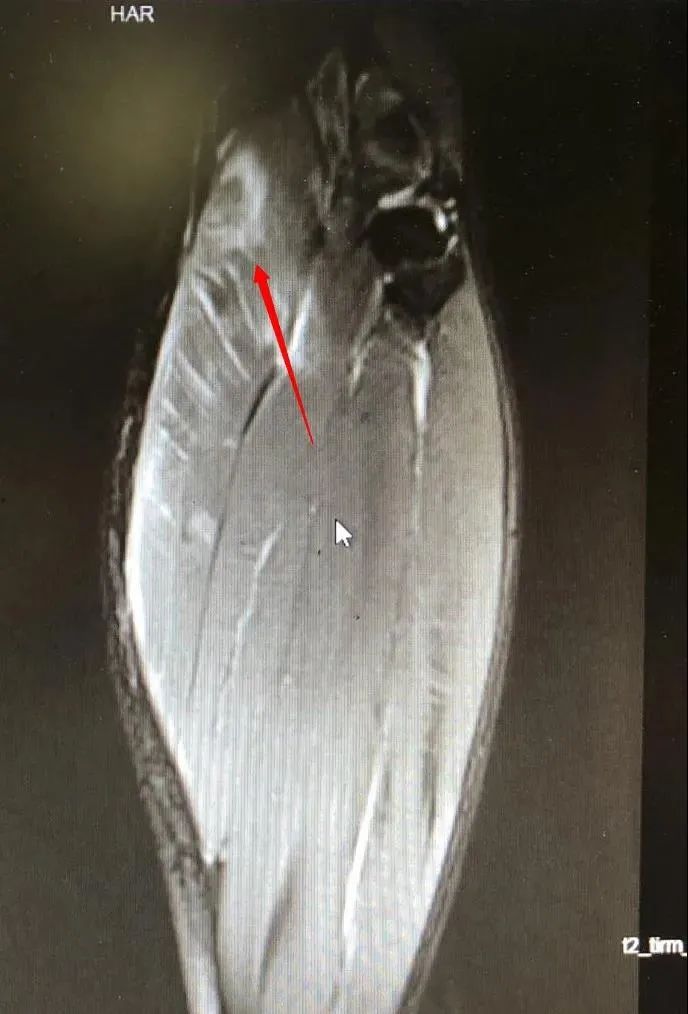

在该院运动医学科,李先生被诊断为腓肠肌群急性损伤。张青松主任介绍说,腓肠肌群是由位于小腿后方的腓肠肌以及腓肠肌下方的比目鱼肌组成的一组肌群,也就是通常我们说的“腿肚子”,由膝关节后方经小腿后方向下延伸到足跟。

腓肠肌群损伤就是该肌群肌肉和肌腱部分受到过分牵拉,甚至发生肌纤维撕裂。其中,大多数是由于膝关节伸直时再突然蹬地提踵所致。另外,在膝关节伸直位时,严重的外翻或者内翻也会导致腓肠肌内侧头或外侧头损伤。

这种伤病在各种球类、跑步、跳远跳高等体育运动中都很常见,特别是网球运动中,因此也有“网球腿”的俗称。伤者在受伤瞬间往往会感到小腿后侧的打击感,甚至听见弹响,就像被人踢了或者用棍子敲击一样,疼痛部位常处于小腿后方中点稍内侧。